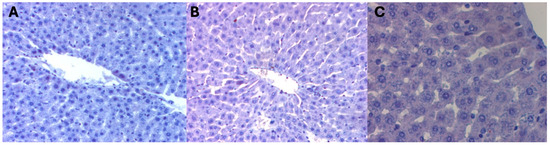

There was no difference between the groups on assessment of the mean surface areas of liver preparations occupied by a positive immunohistochemical reaction for beclin 1 in the livers of female rats from control groups, i.e., not subjected to hyperbaric treatment. The color reaction for beclin 1 was not visible on any of the observed liver preparations (Figure 1) (Table 1).

Figure 1. (A) KI control group. Invisible immunohistochemical reaction for beclin 1 in the liver fragment of a female rat that was decapitated on the 1st day of the experiment. H + AEC dyeing. (B) KII control group. Invisible immunohistochemical reaction for beclin 1 in a fragment of the liver of a female rat that was decapitated on the 5th day of the experiment. Dyeing H + AEC. (C) KIII control group. Invisible immunohistochemical reaction for beclin 1 in a fragment of the liver of a female rat that was decapitated on the 10th day of the experiment. Dyeing H + AEC.